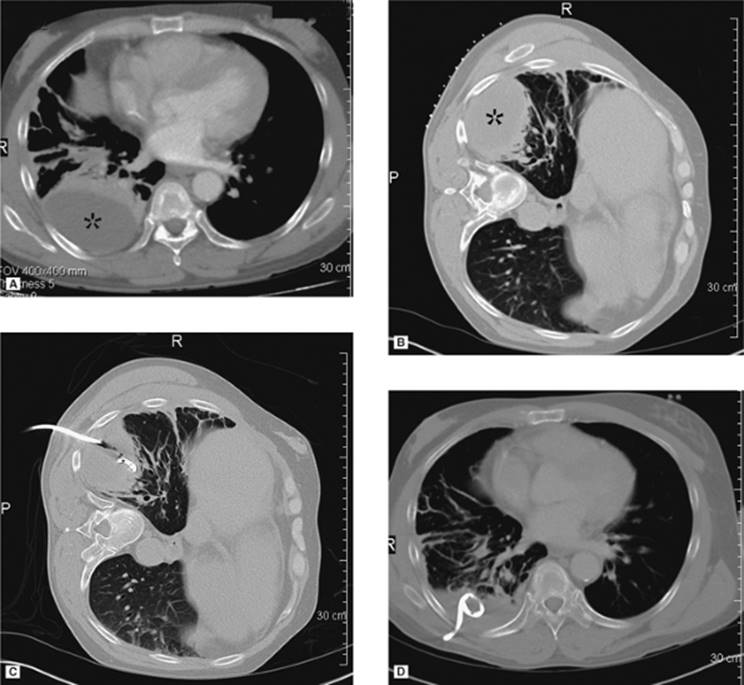

000159

Figure 35.5. A 19-year-old patient with sepsis and cough. A: Axial CT at the level of the midchest demonstrates an 8.5-cm fluid collection in the right posterior hemithorax (asterisk) with compression atelectasis of the adjacent lung. Direct percutaneous access is blocked due to inferior margin of the scapula, overlying ribs, and aerated lung. B: Patient was placed in a left-side-down decubitus position. Change in position provides direct posterior access to the fluid collection. A localizer grid has been placed to mark site of access. C: Access gained with micropuncture needle system and then a 14 Fr drain placed over a wire. Fluid aspirated with syringe and then drain was secured in place and connected to suction bulb. D: Postdrain placement CT. (Case courtesy of Lauren Alexander, MD, Gainesville, FL.)

If a pneumothorax occurs in association with thoracic intervention, or secondary to underlying lung disease, a chest tube/pleural catheter may be required. The indications for tube placement include size of pneumothorax greater than 25%, pain, shortness of breath, or progressive enlargement on serial radiography. These tubes are easily placed in the second or third intercostal space anteriorly. Our preference is to place an 8 French catheter under fluoroscopic guidance using the Seldinger technique to avoid injury to the adjacent lung. We gain access with a 4 French micropuncture system (Angio Dynamics, Queensbury, NY) followed by insertion of a 0.035 guidewire over which the chest tube is advanced. This is secured in place with nonabsorbable suture and covered with petroleum jelly gauze to decrease the risk of air leak. Most of the pneumothorax is aspirated using a 60-mL syringe with the aid of a three-way stopcock. Then the tube is connected to a Pleur-Evac drainage system as is done with surgically placed chest tubes. The pleural catheter remains in place until there is no significant residual pneumothorax and there is no evidence of air leak when the tube is connected to water seal (Fig. 35.7A–C).

000193

Figure 35.6. Ultrasound image showing typical appearance for thoracentesis guidance. The central target (pleural effusion) is identified by an asterisk, lung margin by arrowheads, and drainage catheter pathway with an arrow.